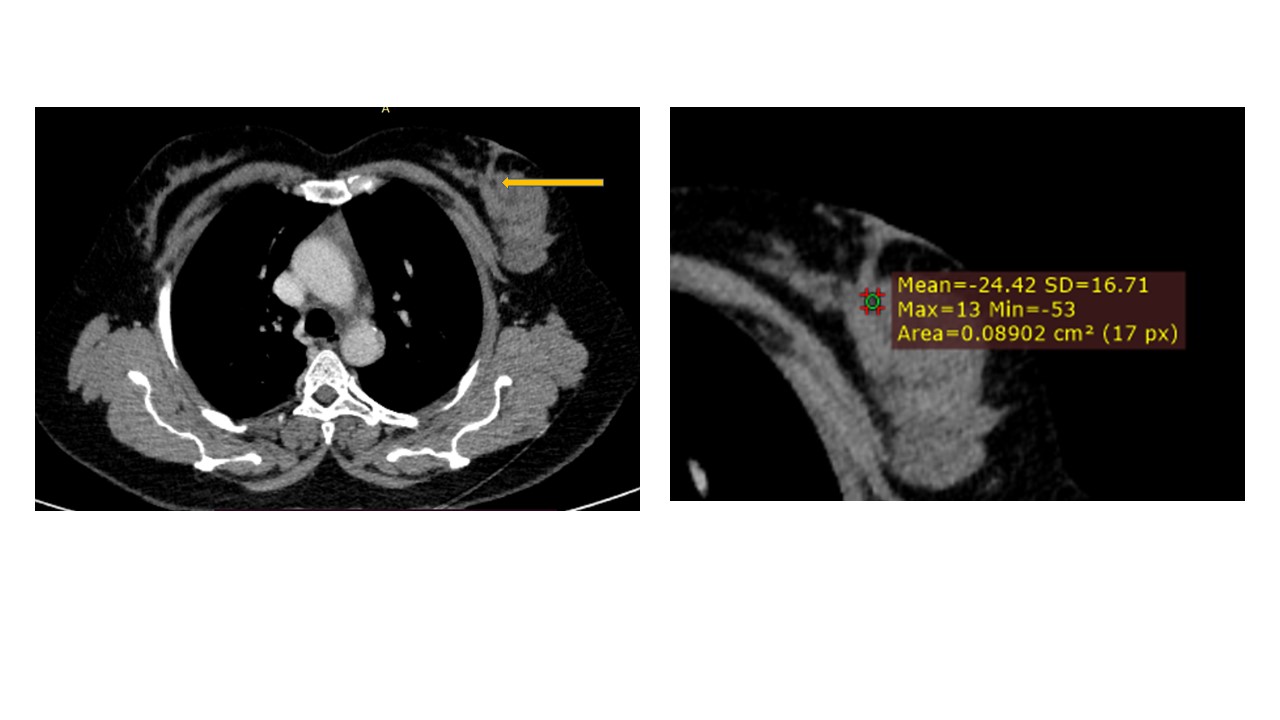

Physical examination revealed a 6.0?×?5.0 cm mass in the left breast. Mammography demonstrated an irregular, fat-containing, heterogeneous mass with circumscribed margins in the upper outer quadrant of left breast. Few scattered foci of coarse calcification were present within the mass. Breast sonography revealed an irregular, parallel, hyperechoic mass with circumscribed margins and no posterior acoustic features in the left breast at 3 o’clock position. Mild vascularity was observed on Color Doppler imaging. Contrast enhanced ultrasound (CEUS) done out of academic interest showed ill-defined, heterogenous enhancing mass, showing irregular shape, having surrounding vessels. Quantitative analysis showed higher PI (pulsatility index), AUC (area under curve) and lower TTP (time to peak) compared to normal tissue. The mass was assessed as Breast Imaging Reporting and Data System category 4b, and ultrasound-guided 14-gauge core biopsy revealed a biphasic tumor composed of bilayered ductal epithelium compressed by the proliferating stroma into leaf like architecture, The stromal cells showed increased cellularity, marked nuclear atypia and pleomorphism with round to oval nuclei, opened up chromatin, prominent nucleoli and moderate to abundant cytoplasm with many bizarre looking tumor giant cells. The stroma showed extensive heterologous lipomatous differentiation composed of neoplastic adipocytes as well as few lipoblasts. Mitosis was 3-4/10/hpf. Final histopathological diagnosis of malignant Phyllodes tumor with liposarcomatous differentiation was given. CT scan chest was done to look for lung metastasis, which revealed an irregular soft tissue mass in left breast with internal focal areas of fat attenuation. No nodules were seen in the lungs. Subsequent lumpectomy was performed and the gross specimen showed a well-demarcated tumor, measuring?6.8?×?6.5 × 3 cm. There were considerable bright yellow fatty components and some cleft-like spaces. Microscopically, the tumor exhibited a typical leaf-like growth pattern with extensive stromal overgrowth and stromal hypercellularity. Extensive areas of lipomatous differentiation were seen ranging from mature adipocytes to lipoblasts showing marked stromal atypia and irregularity. Mitotc activity was 7-8/10hpf. IHC for MDM2 was negative. Overall features were of malignant phyllodes tumor with well differentiated liposarcomatous differentiation.